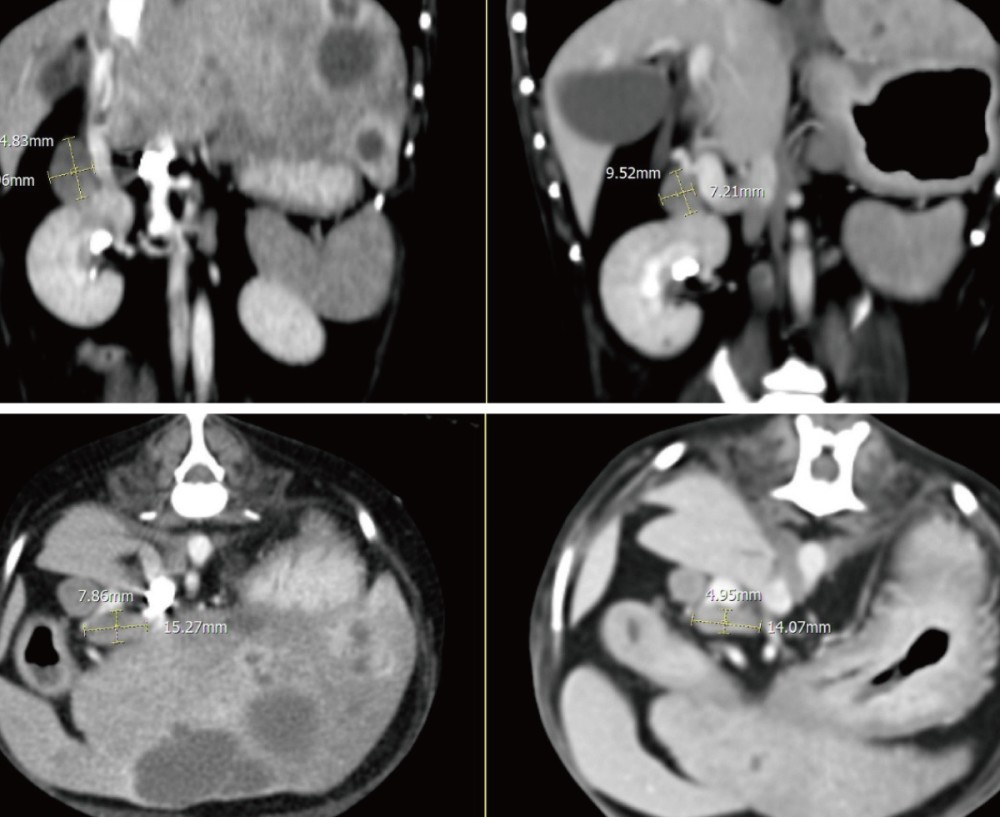

추가로 CT를 시행하였으며, 그 결과 간 실질 내 다발성 낭성 병변과 함께 췌장 석회화, 총담관 확장, 담석이 확인되었습니다.

실제로 추적 CT에서도 간 내 낭성 병변의 크기가 뚜렷하게 감소하고 림프절 크기 또한 감소하여 처치에 대한 반응이 명확하게 확인되었습니다 .

▲ 좌측 내측엽과 가측엽에 위치하던 cystic lesion의 크기 뚜렷한 감소 및 불규칙한 변연으로 변화

▲ 이전 검사에서 뚜렷하게 종대되어 관찰되었던 간 림프절 크기 감소